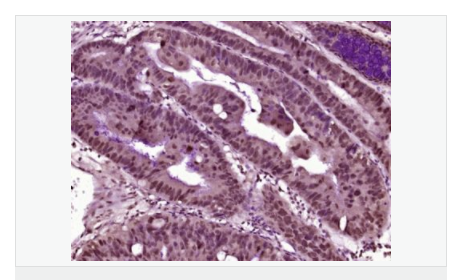

產(chǎn)品應用ELISA=1:5000-10000 IHC-F=1:100-500 ICC=1:100-500 IF=1:100-500 (石蠟切片需做抗原修復)

image.png